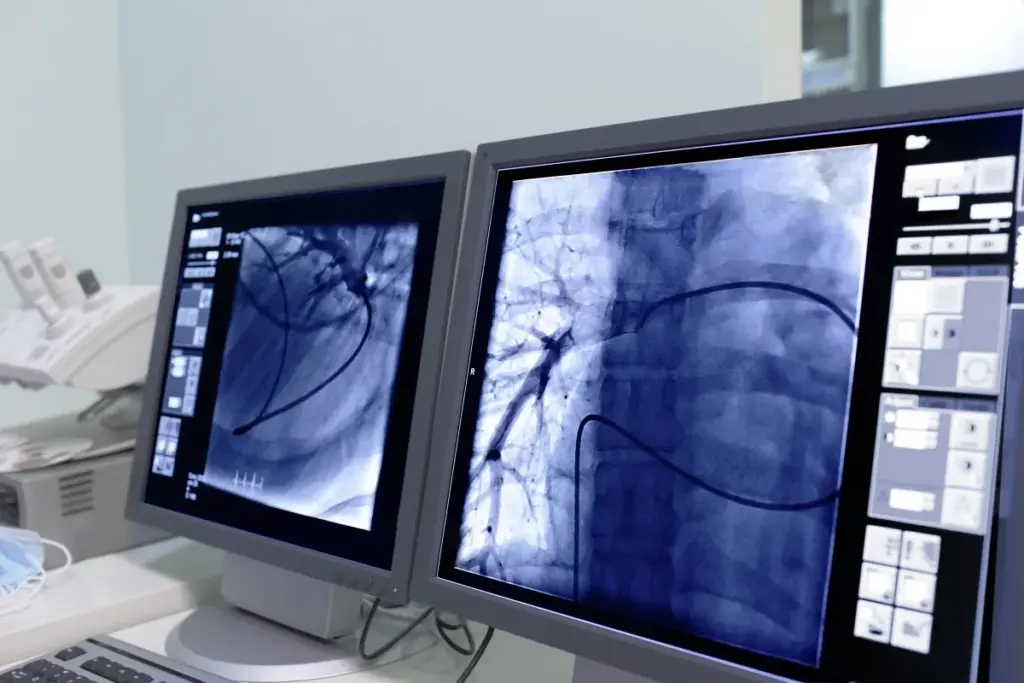

Is a CT Angiogram Painful?<image1>

When we talk about heart health, pain worries are common. A CT angiogram is a non-invasive test. It uses X-rays to show the heart and blood vessels clearly. It’s often chosen over heart cath or catheterization because it doesn’t need a catheter in a cath lab.

A CT angiogram is a detailed medical imaging test. It shows the heart and blood vessels clearly. This test has significantly transformed cardiology by providing doctors with detailed insights into the heart system.

A CT angiogram is a non-invasive test. It uses X-rays to show the arteries and veins. It helps find problems like coronary artery disease, aneurysms, and blockages.

For a CT angiogram, a dye is injected into a vein. This dye makes the blood vessels stand out. The CT scanner then takes X-ray images from different angles.

These images are turned into 3D pictures. This lets doctors see the blood vessels and any problems.